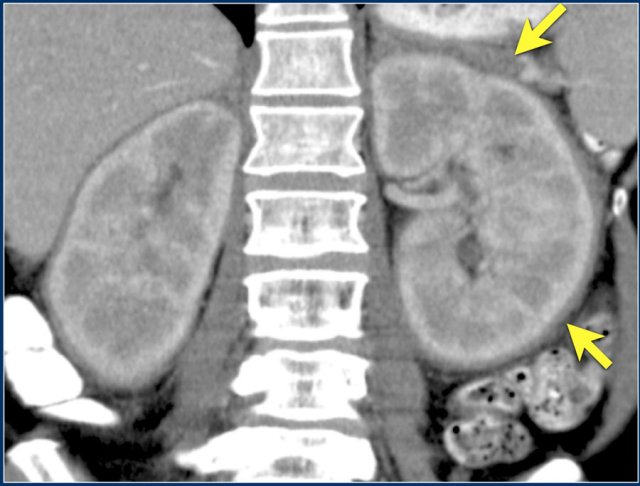

Here a patient with lung cancer.

There is a metastasis in the left kidney and there are multiple lymph node metastases (arrows).

If this was the only presentation, it would be difficult to differentiate from a renal cell carcinoma with lymph node metastases.